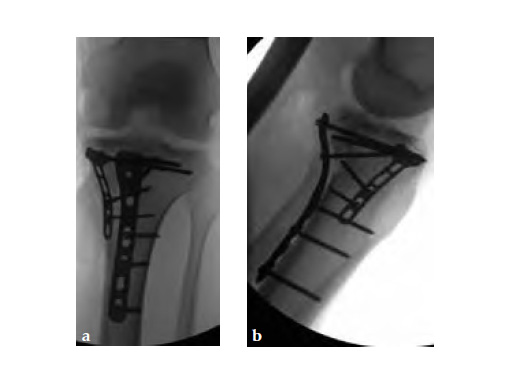

A 33-year-old male was involved in an altercation and suffered a gun shoot wound to his knee

Case provided by Brent Norris, Tulsa, USA.

Initially taken for incision and drainage and then ORIF . Patient placed in a floppy lateral position with the effected lower extremity externally rotated (opposite hip and shoulder bumped up about 3040) allowing exposure of the posterior medial knee. A posterior medial and an anteromedial incision were used to repair the fracture with a 67 cm skin bridge.

Postoperative healing was uneventful and the patient had no complications.